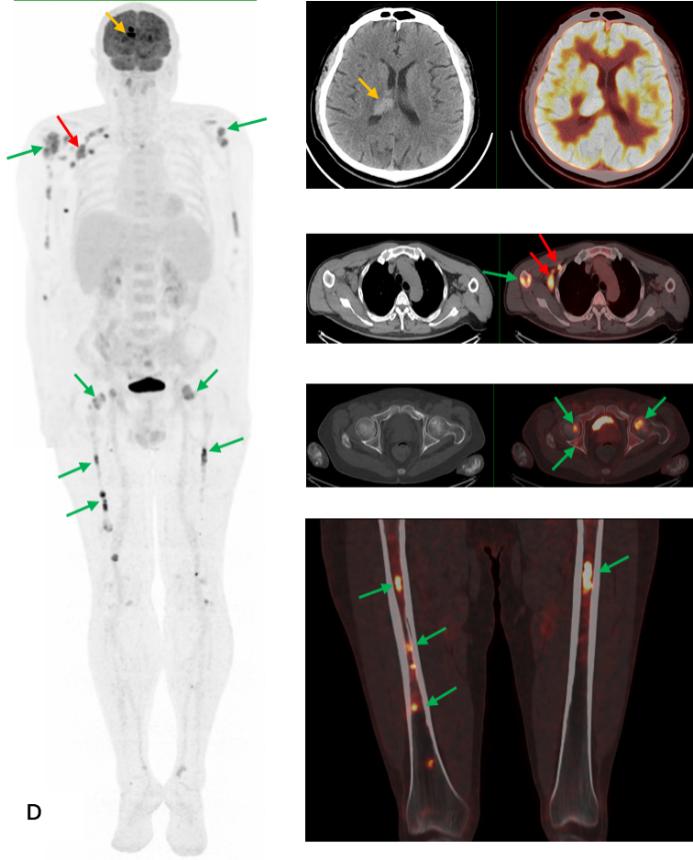

前列腺M(fèi)RI示:前列腺移行帶結(jié)節(jié)狀異常信號(hào),建議穿刺活檢;前列腺增生,PI-RADS2;雙側(cè)股骨頭信號(hào)異常,不排除轉(zhuǎn)移瘤(圖A)。為評(píng)估骨轉(zhuǎn)移情況遂行ECT全身骨顯像檢查,示:雙側(cè)肱骨頭、雙側(cè)股骨頭、右側(cè)前臂上段、右側(cè)股骨中下段代謝異常增強(qiáng)(圖B)。骨顯像不符合前列腺癌骨轉(zhuǎn)移典型表現(xiàn),同時(shí)結(jié)合患者胸部CT(圖C)平掃示右側(cè)腋窩多發(fā)淋巴結(jié)腫大,生化檢查示乳酸脫氫酶620U/L(97-270),懷疑系血液系統(tǒng)腫瘤,建議患者行PET/CT檢查。PET/CT示:右側(cè)腦室內(nèi)高密度灶,多發(fā)FDG代謝增高淋巴結(jié)及多發(fā)骨骼/骨髓FDG代謝增高灶,考慮淋巴瘤(圖D)。

PEC/CT檢查右側(cè)腦室內(nèi)高密度灶(黃箭),多發(fā)FDG代謝增高淋巴結(jié)(紅箭)及多發(fā)骨骼/骨髓FDG代謝增高灶(綠箭),同機(jī)CT平掃示相應(yīng)骨骼未見(jiàn)明顯破壞,考慮淋巴瘤。

患者后在局麻下行右胸壁下淋巴結(jié)切除活檢術(shù),術(shù)后病理示:彌漫大B細(xì)胞淋巴瘤,生發(fā)中心來(lái)源。